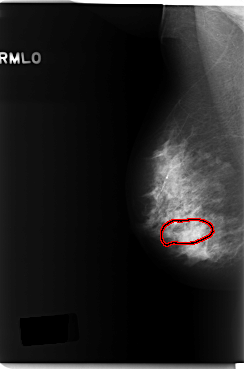

C_0232_1.RIGHT_MLO

RIGHT_MLO LINES 5904 PIXELS_PER_LINE 3904 BITS_PER_PIXEL 12 RESOLUTION 50 OVERLAY

FILE: C_0232_1.RIGHT_MLO.OVERLAY

TOTAL_ABNORMALITIES 1

ABNORMALITY 1

LESION_TYPE CALCIFICATION TYPE FINE_LINEAR_BRANCHING DISTRIBUTION SEGMENTAL

ASSESSMENT 5

SUBTLETY 4

PATHOLOGY MALIGNANT

TOTAL_OUTLINES 1

BOUNDARY